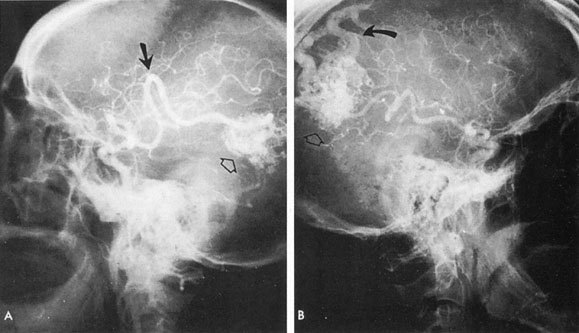

Tortuous or redundant basilar arteries are not uncommon in the older age group. Occasionally, gross dilation or ectasia develops so that the basilar artery acts as a mass in the posterior fossa. This phenomenon produces signs of low-pressure hydrocephalus, cranial nerve palsies, and long tract and sensory signs and may even simulate a cerebellopontine angle tumor or tumor at the foramen magnum.58 It is possible to diagnose such lesions with CT59 or MRI60 but angiography is definitive (Fig. 6). The association of insidious multiple cranial nerve palsies and long tract signs referable to a brainstem level, in an elderly patient with evidence of atherosclerosis, should make fusiform basilar artery dilation a diagnostic consideration.

Fig. 6. Fusiform basilar dilation. A: Lateral projection vertebral arteriogram showing a widened basilar artery (arrow) projecting beyond level of dorsum sellae. B: Anteroposterior projection showing a widened and tortuous basilar artery.